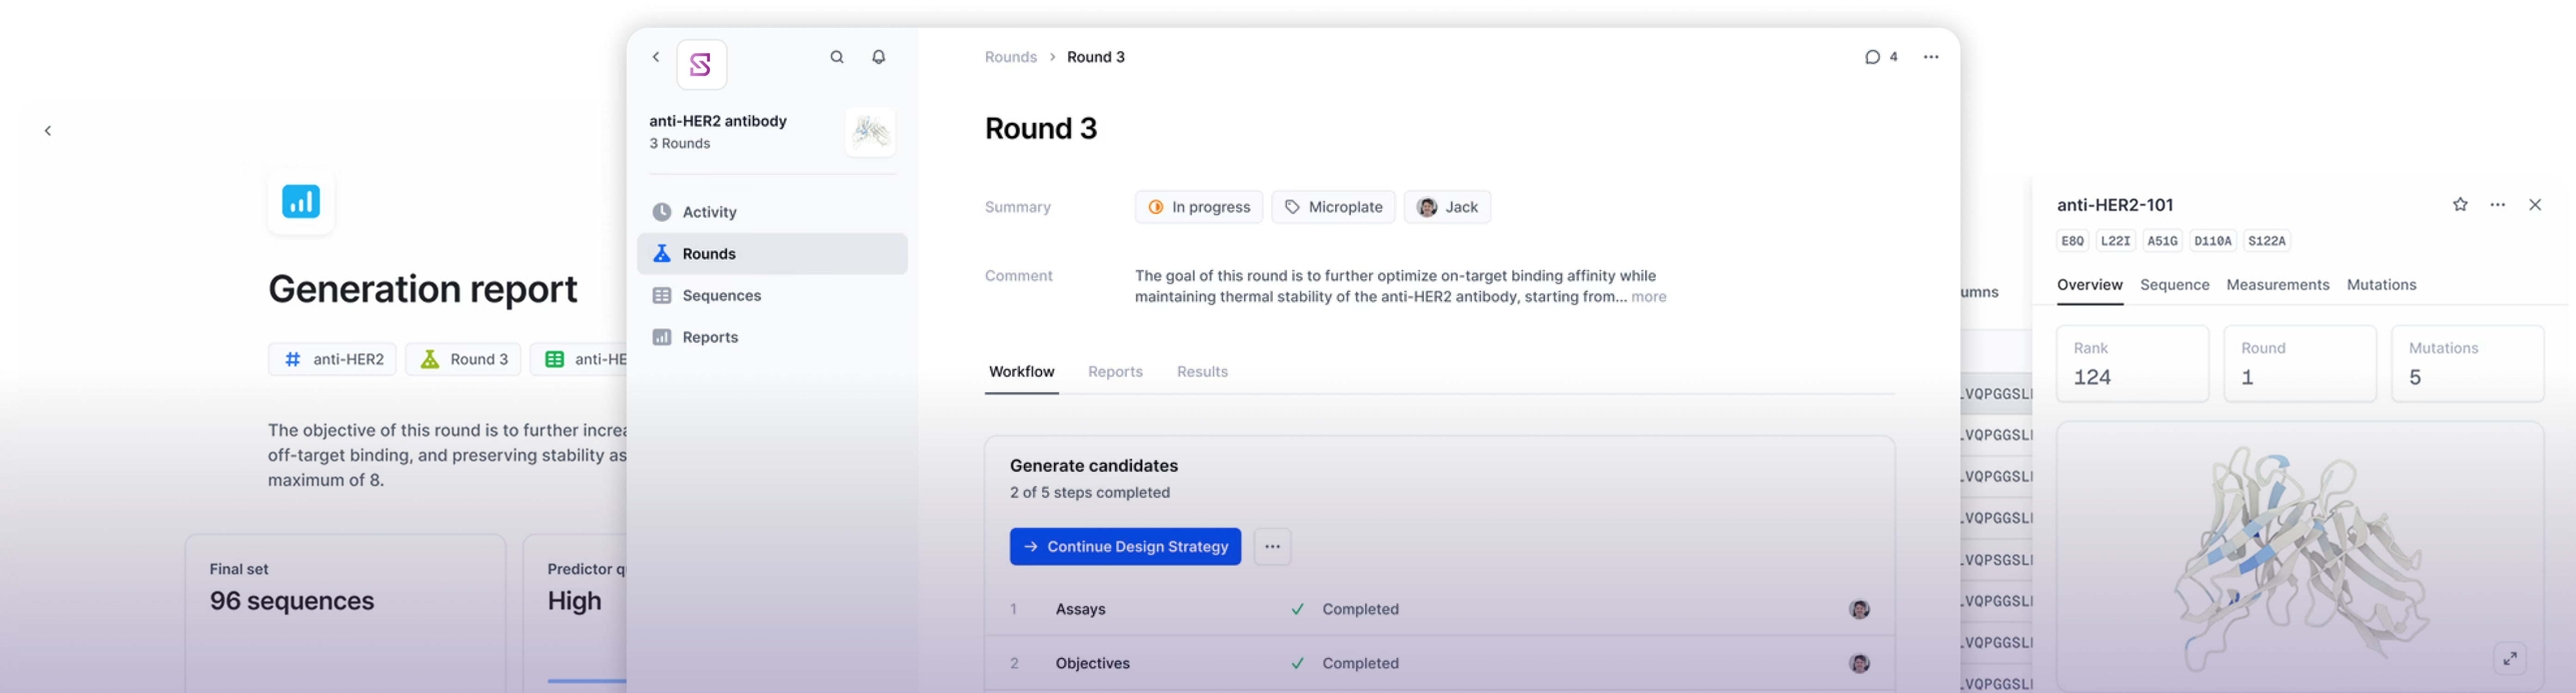

SOPHIA AI

Messaging Platform

Round Progress

AI Messaging & Automation Platform

Multi-tenant messaging platform with AI-powered automation, built to handle thousands of concurrent workflows across enterprise clients.